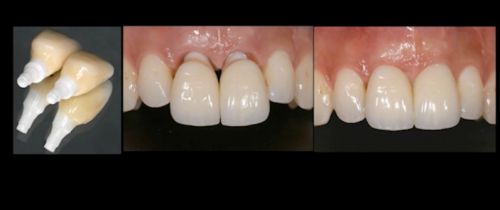

Далее фиксируем провизорную (временную) коронку и с ее помощью за несколько визитов формируем десневой контур. С провизорной коронкой необходимо ходить около 3 месяцев и только по истечении этого срока фиксируют изготовленную зубным техником, постоянную реставрацию (коронку).

Фото. Сформированные мягкие ткани готовы для фиксации постоянных коронок.

Фото. Фиксированы постоянны цельно-керамические рестарвации (коронки).

Так выглядит современный протокол по замещению имплантатом одного зуба

Коронка на имплантате может быть временной на цементной или винтовой фиксации и, позднее, окончательной цельнокерамической или металлокерамической с винтовой или цементной фиксацией.Вид ортопедической конструкции выбирает врач, ориентируясь на глубину расположения платформы имплантата и оси его наклона.